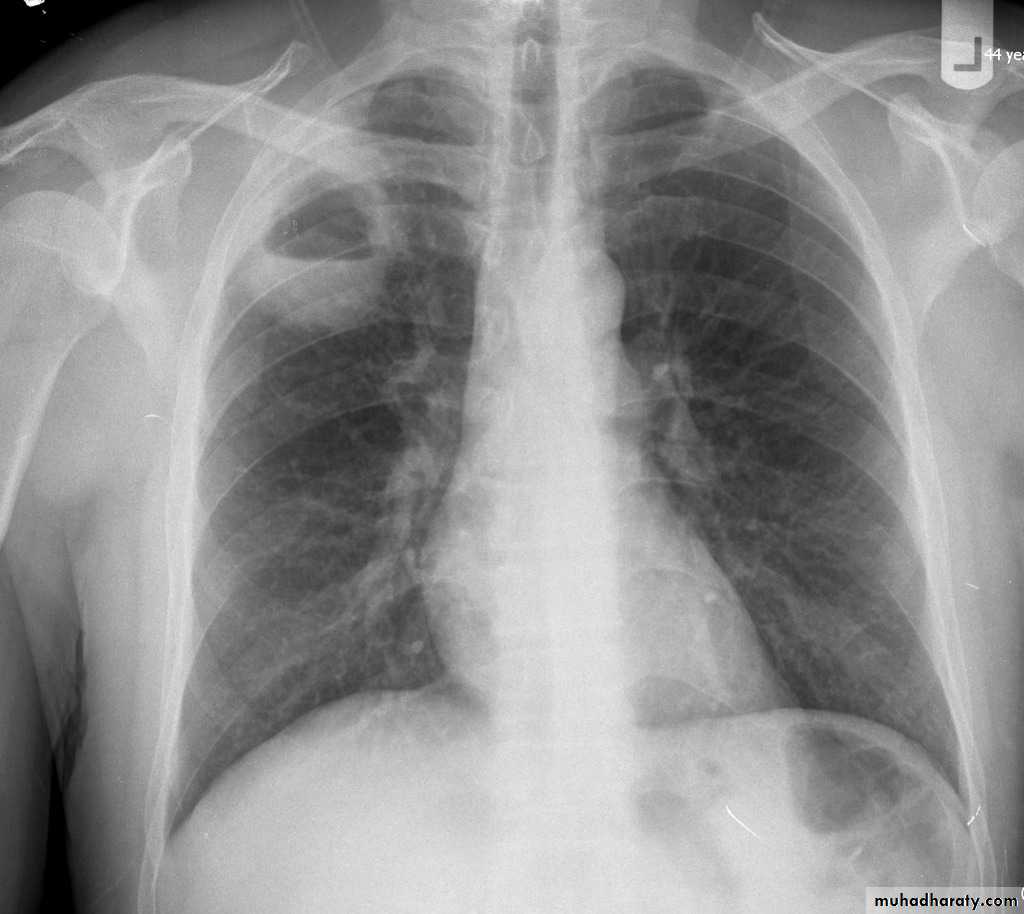

Pulmonary emphysema is defined as the "abnormal permanent enlargement of the airspaces distal to the terminal bronchioles accompanied by destruction of the alveolar wall and without obvious fibrosis". Emphysema is one of the entities grouped together as chronic obstructive pulmonary diseaseRadiographic features

Plain film

Except in the case of very advanced disease with bulla formation, chest radiography does not image emphysema directly, but rather infers the diagnosis due to associated features :

hyperinflation:

1.flattened hemidiaphragm(s): most reliable sign

2.ncreased and usually irregular radiolucency of the lungs

9.vascular changes paucity of blood vessels ( absent pulmonary markings in outer 1/3 of the lung fields )